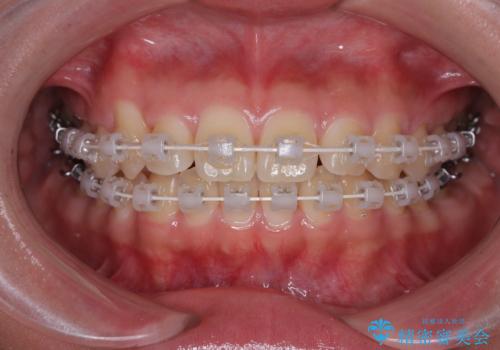

- 上下前歯のデコボコを気にして来院された患者様です。

ワイヤー矯正でもマウスピース矯正でも可能でしたが、短期間で、自身の手を煩わせることなく治療を行いたいとのことで、ワイヤー装置にて矯正治療を行うこととしました。

僅か8ヶ月という短期間で、綺麗な歯列に仕上がりました。